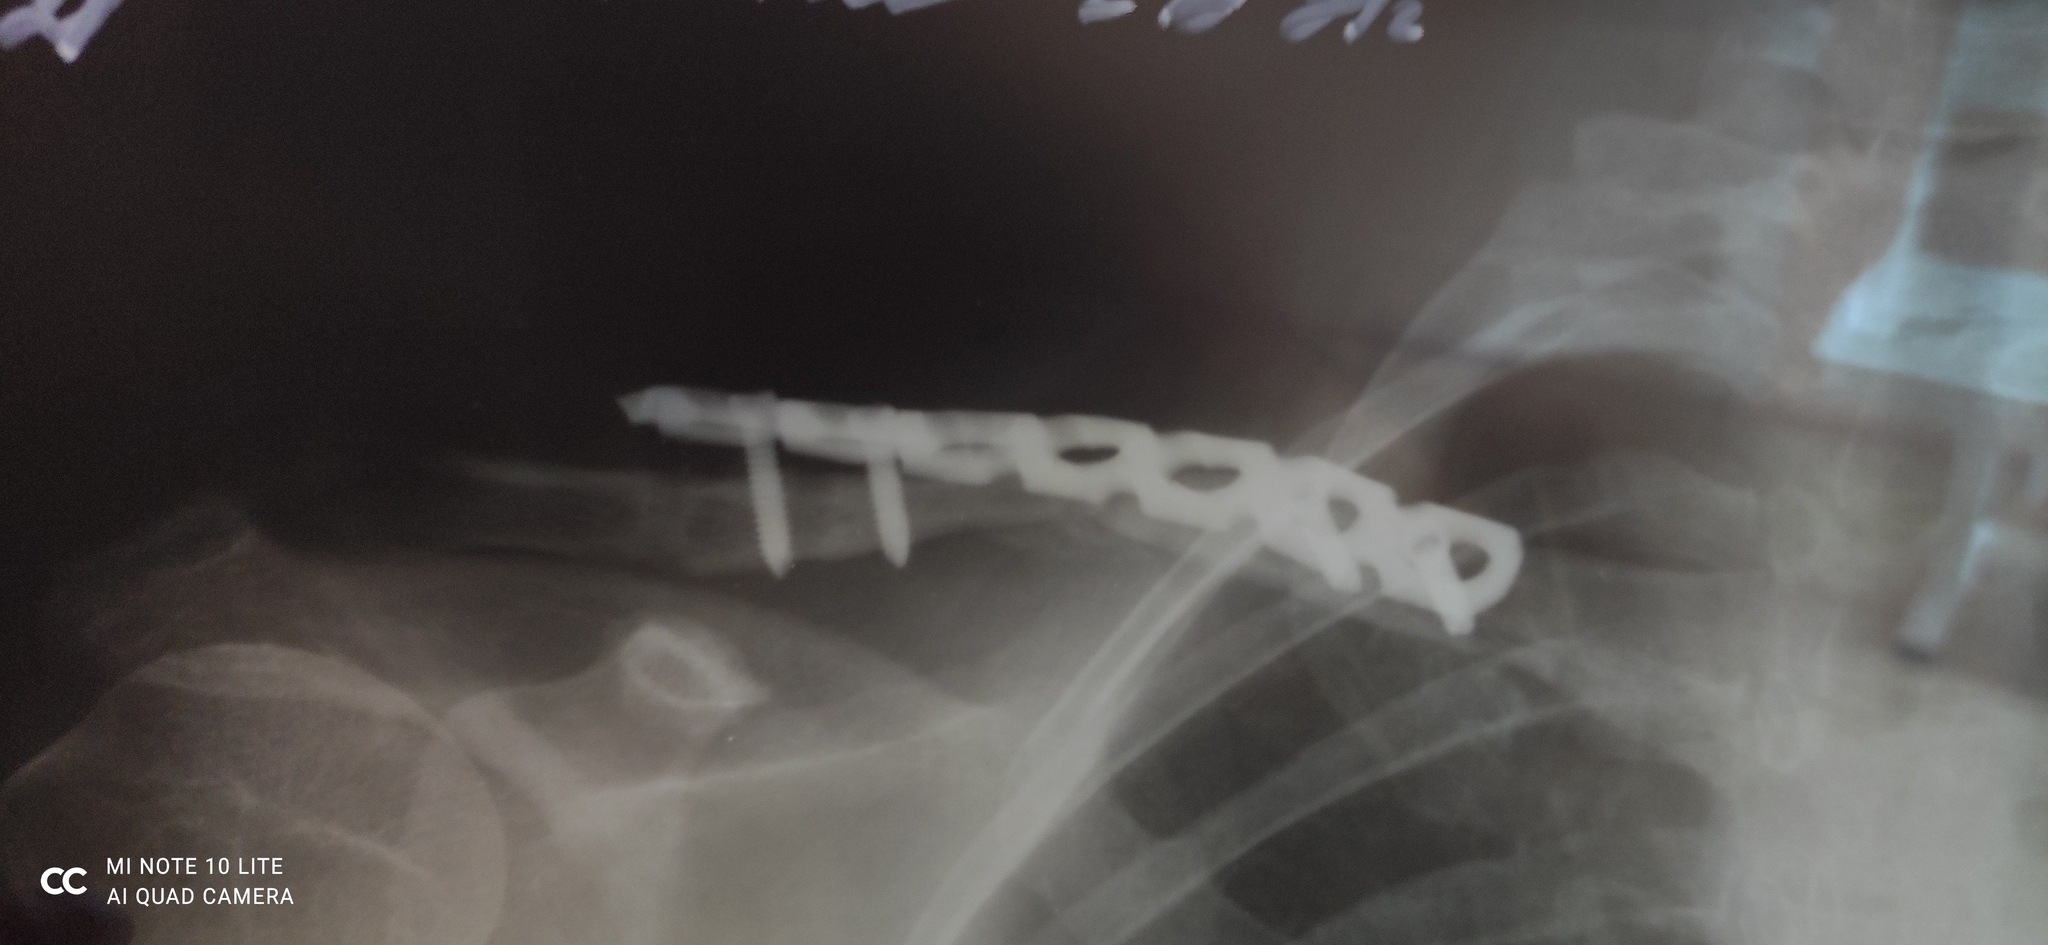

Случился перелом ключицы, сделали операцию, поставили пластину. Все ок. Сказали, что через год можно убирать.

Я проходила 1.5 года. Был некий дискомфорт и внешне пластина стала выпирать. Врач в поликлинике сказал, что все зажило и саморезы начали «выходить» из кости и если я хочу, можно уже убрать пластину.

Итог поставили другую пластину. Так скажем более неудобную и выпирающую, т.к. в ключице и так были дырки от прошлой, кое как эту прикрутили.